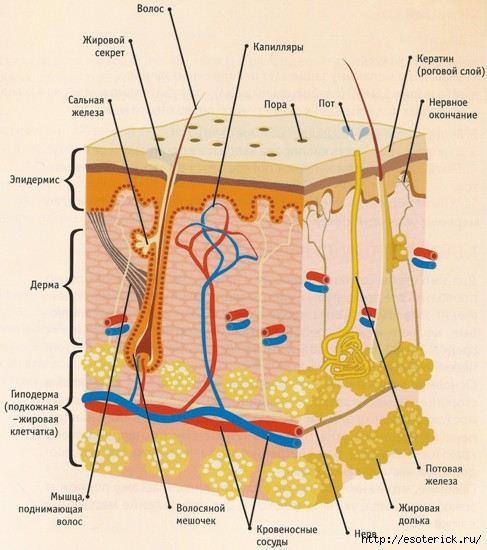

Проблемы с кожей и их психологические причины |

Это цитата сообщения esoterick [Прочитать целиком + В свой цитатник или сообщество!]

Вы страдаете от кожных заболеваний, таких как псориаз, экзема, сыпь или прыщи? Если да, то было бы целесообразно сосредоточиться на том, почему, несмотря на лечение, часто не происходит никаких изменений.

Проблемы с кожей и их психологические причины

Наверняка сейчас уже все знают (или хотя бы слышали), что психика тесно связана с телом, поэтому психические проблемы отражаются и на теле. Я уже публиковал на своих сайтах статьи о психологических причинах болезней, и вот мне попалась еще одна интересная статья – теперь насчет кожных заболеваний.